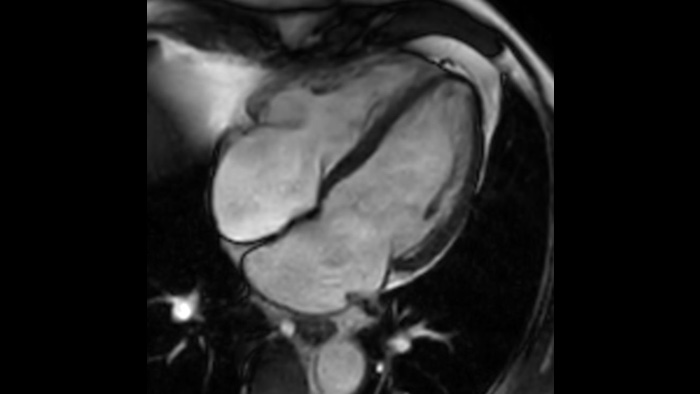

Comfort per il paziente Riduzione fino al 40% delle apnee, con una qualità dell'immagine pressoché identica.3

1 Anche nella remota eventualità che venga meno la tenuta ermetica del magnete, la fuoriuscita di una quantità trascurabile di elio non influirebbe in modo sostanziale sul livello di ossigeno presente nella sala. 2 Rispetto alle scansioni Philips senza Compressed SENSE. 3 Per una frequenza cardiaca bassa (50 bpm), rispetto alle scansioni Philips senza Compressed SENSE. 4 In scansioni 3D MSK VIEW isotropiche, rispetto alle scansioni Philips senza Compressed SENSE.